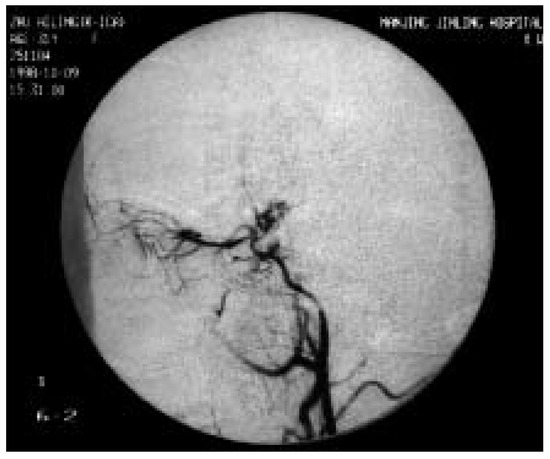

Moyamoya disease and migraine-like headaches

by X.-F. Liua and D. K. Jung

Swiss Arch. Neurol. Psychiatry Psychother. 1999, 150(6), 272-274; https://doi.org/10.4414/sanp.1999.01123 - 1 Jan 1999

Cited by 5 | Viewed by 30

Rarely, adult moyamoya disease presents with recurrent migraine-like headaches during a long course.We report the case of a 31-year-old woman with moyamoya disease and migraine-like headaches, with a 13-year history. Physical examination showed no neurologic deficits. Magnetic resonance angiography (MRA) and digital subtraction [...] Read more.

Rarely, adult moyamoya disease presents with recurrent migraine-like headaches during a long course.We report the case of a 31-year-old woman with moyamoya disease and migraine-like headaches, with a 13-year history. Physical examination showed no neurologic deficits. Magnetic resonance angiography (MRA) and digital subtraction angiography (DSA) showed occlusion of the right internal carotid artery (ICA), severe stenosis of the left ICA, and abnormal vascular network at the base of the brain. The calcium channel blocker, nimodipine, was introduced in order to prevent further symptoms. After the introduction of nimodipine, no further headache, weakness and numbness of the left hand occurred in this patient. This suggests that migraine-like headaches may be caused by moyamoya disease and that nimodipine may have a beneficial effect on this condition. Full article

Show Figures

Figure 1